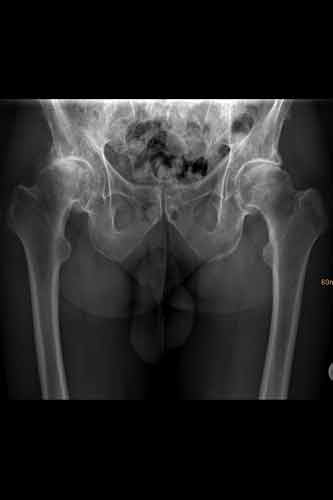

Vorher

Hüftröntgen ap

Coxarthrose Grad 4 links

Coxarthrose beidseits

Beide Hüften wurden in einer Operation ersetzt.